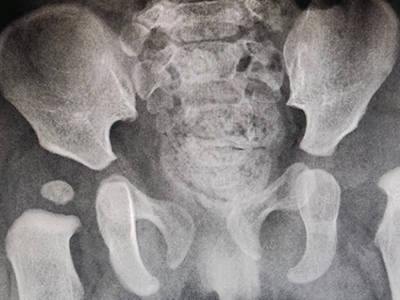

先天性髋关节脱位检查发现股骨头位移图

髋关节脱位进行影像学检查会发现股骨头位移,能看到股骨小转子。此外,患者自觉髋部疼痛,并且伴随压痛,下肢活动受限,需要立即进行手法复位或手术复位。